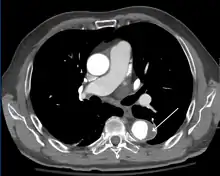

Computed tomography

Computed tomography angiography is a fast, non-invasive test that gives an accurate three-dimensional view of the aorta. These images are produced by taking rapid, thin-cut slices of the chest and abdomen, and combining them in the computer to create cross-sectional slices. To delineate the aorta to the accuracy necessary to make the proper diagnosis, an iodinated contrast material is injected into a peripheral vein. Contrast is injected and the scan performed using a bolus tracking method. This type of scan is timed to injection to capture the contrast as it enters the aorta. The scan then follows the contrast as it flows through the vessel. It has a sensitivity of 96 to 100% and a specificity of 96 to 100%. Disadvantages include the need for iodinated contrast material and the inability to diagnose the site of the intimal tear.

CT with contrast demonstrating aneurysmal dilation and a dissection of the ascending aorta (type A Stanford)